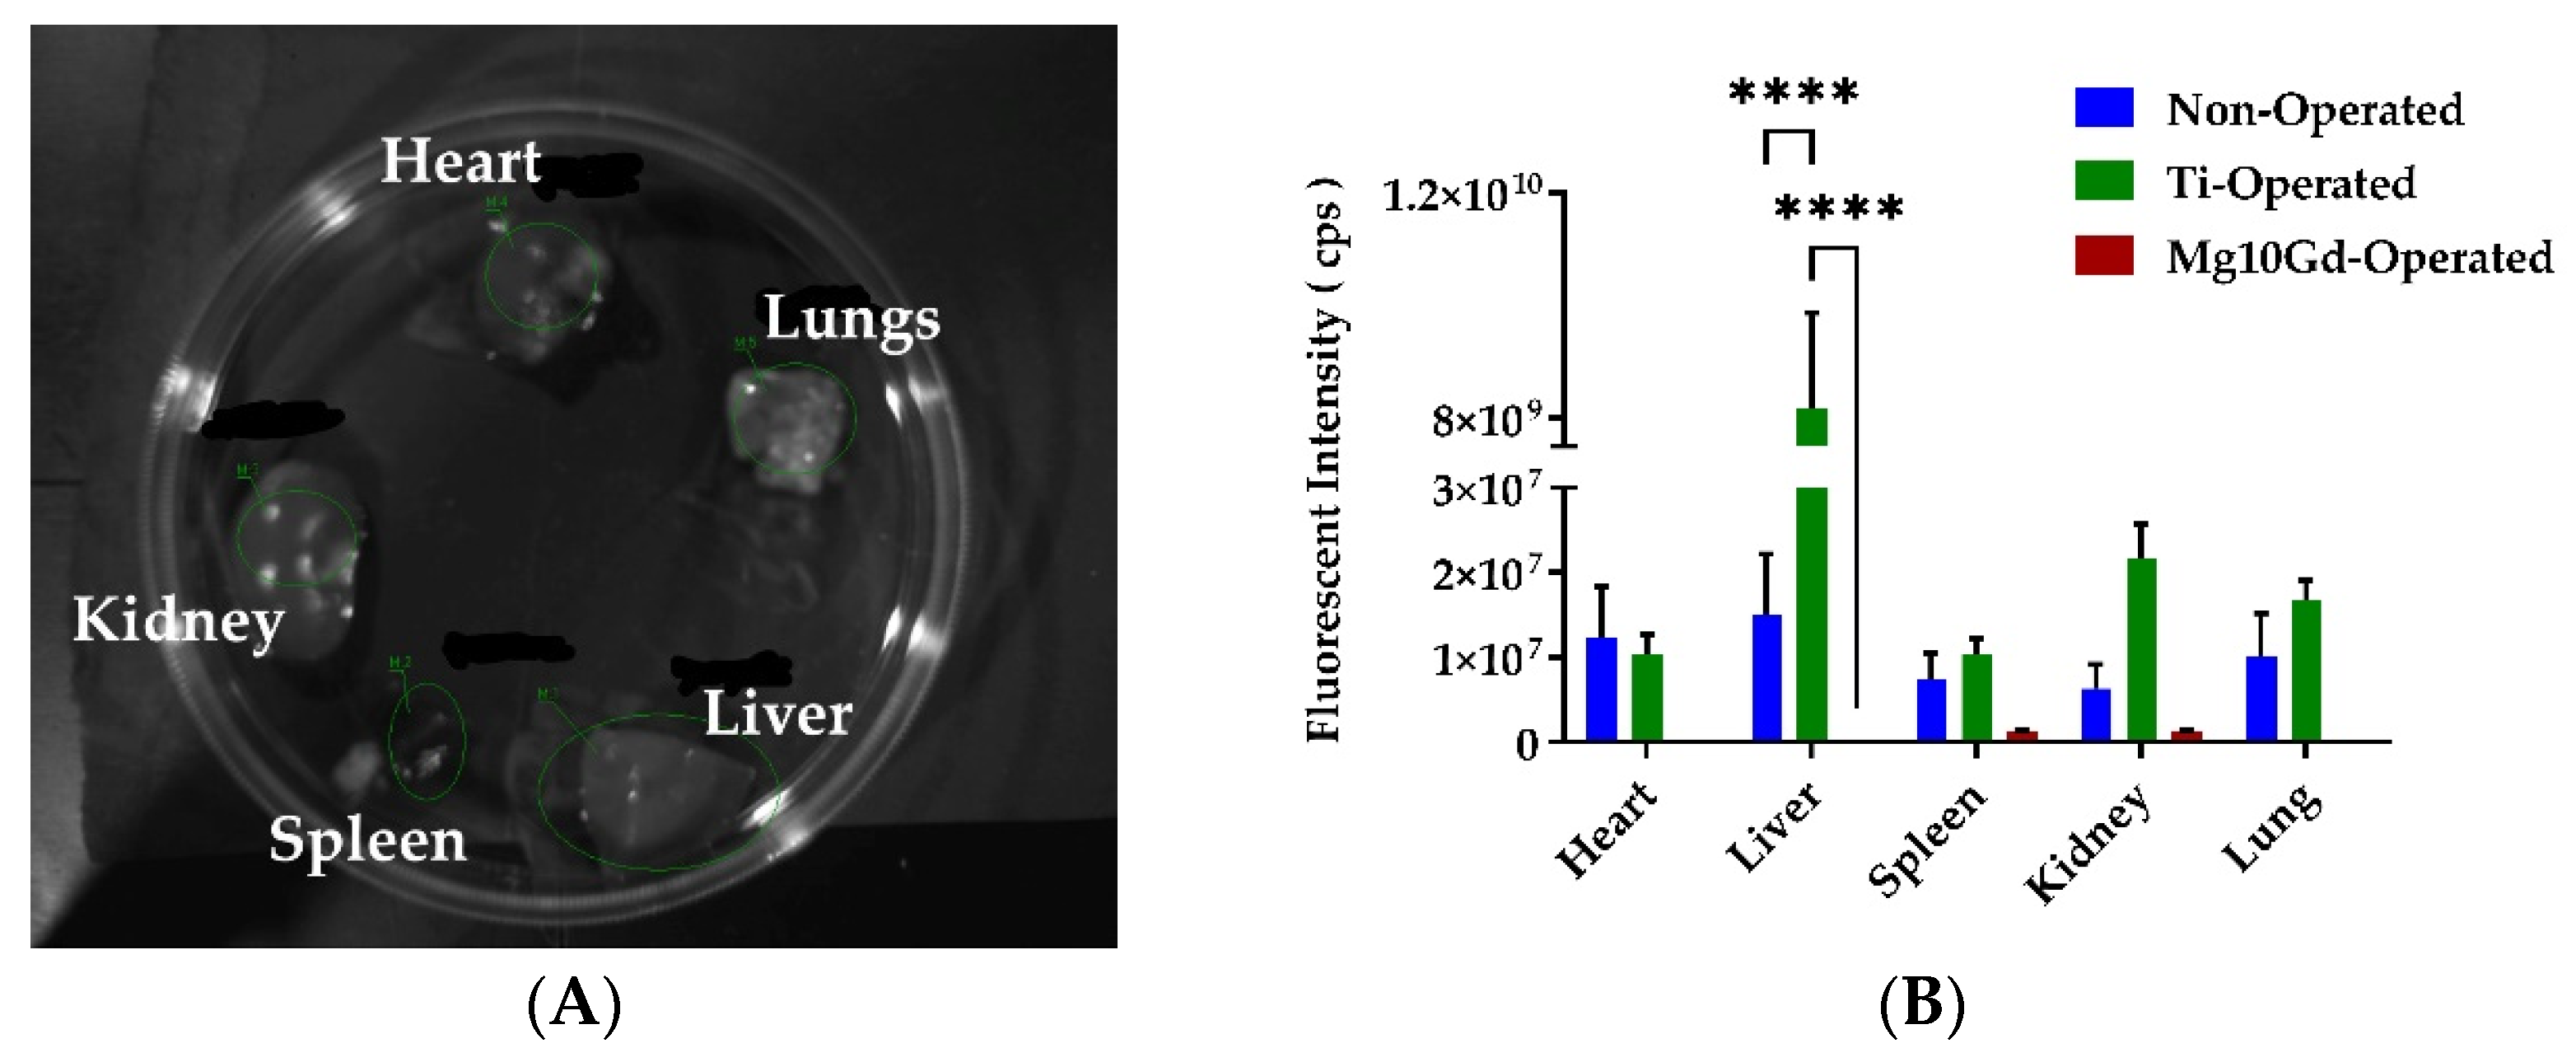

2.3. Ex Vivo Biodistribution Analysis